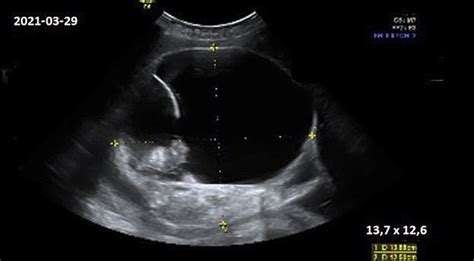

Konkrečiai inkstų geldelių dydžiui įvertinti naudojamas ultragarsas. Nėštumo metu, ypač 18-20 nėštumo savaitę atliekama išsami ultragarsinė patikra, kurios metu detaliai matuojamas vaikelio dydis. Inkstų geldelių dydis paprastai matuojamas milimetrais.

- Normalus vaisiaus inksto geldelės dydis: Įprastai, inksto geldelės dydis iki 7 mm laikomas norma. Tačiau šis rodiklis gali šiek tiek skirtis priklausomai nuo nėštumo savaitės ir individualių vaisiaus ypatumų. Kai kuriais atvejais, pavyzdžiui, berniukams, nestipriai padidėjusios geldelės gali būti laikinos ir praeiti savaime po gimimo.

- Padidėjęs matmuo: Jei matmenys viršija normą (pvz., 7.2 mm, 9.7 mm, 10.9 mm, 15.7 mm), tai gali rodyti pieloektaziją ar kitas inkstų anomalijas. Tokiais atvejais paprastai skiriamas nuolatinis stebėjimas kas 4 savaites ar kitais intervalais.